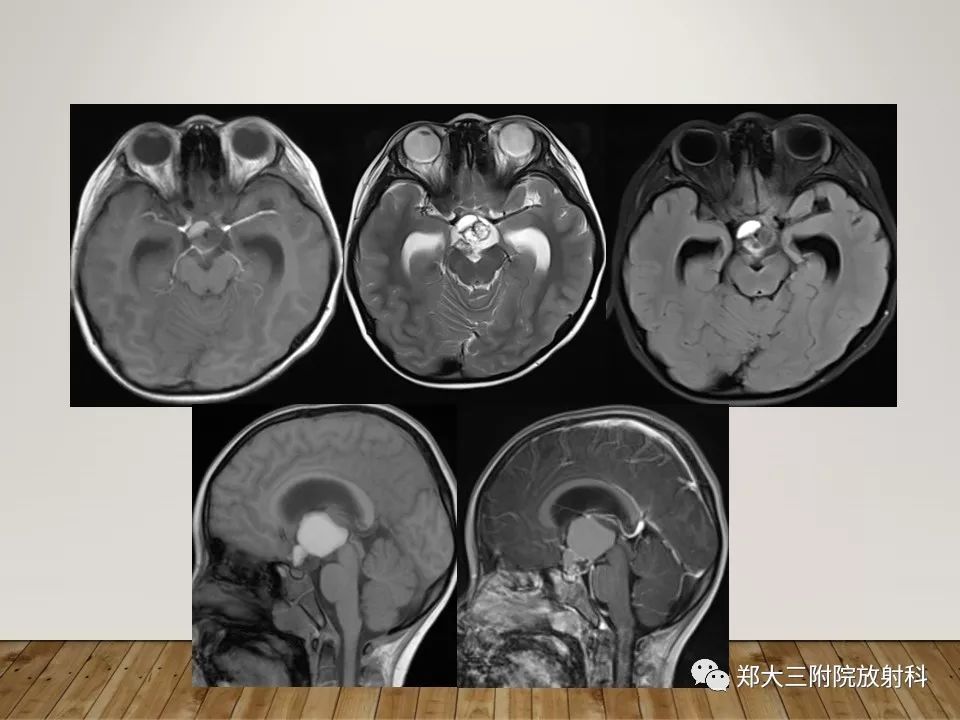

灰结节错构瘤的影像诊断

【PPT】灰结节错构瘤的影像诊断